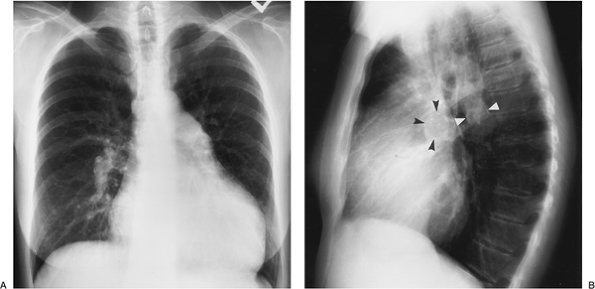

FIGURE 17-26. Primary pulmonary arterial hypertension. PA (A) and lateral (B) chest radiographs of a 54-year-old woman, obtained as part of a workup for lung transplantation, show enlargement of the central pulmonary arteries and narrowing of the peripheral branches. Fine curvilinear calcification can be seen outlining the central pulmonary arteries on the lateral view (arrowheads). There is also enlargement of the right atrium and right ventricle (note increased opacity posterior to the sternum on the lateral view).